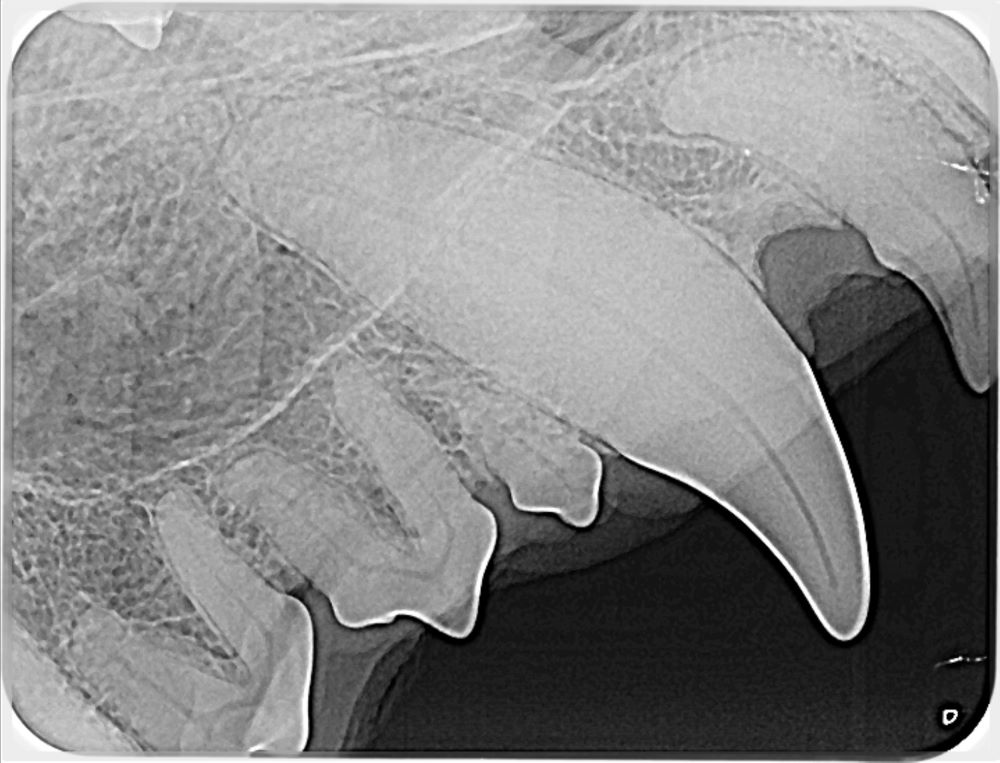

• Intra-oral radiographs

Dental radiograph showing detailed tooth structure

Dental radiograph showing tooth alignment

Dental radiograph showing comprehensive view